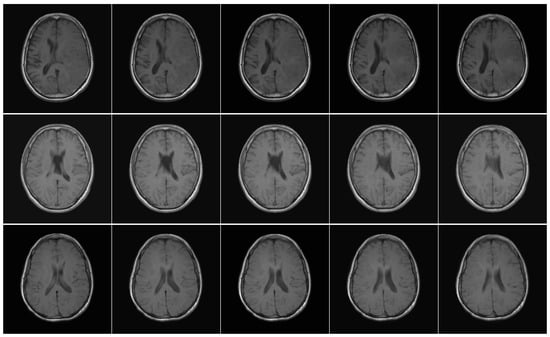

As depicted in Figure 3, the trained model was subsequently validated using EGD to assess its generalisation performance. This validation step allowed for a thorough evaluation of the model in different types of glioma.

Figure 3. Diagram illustrating the proposed method for CNN training and inference. The RSNA-MICCAI data set (top) was used for training on skull-stripped T1w MRI data, while the EGD data set (bottom) was used for inference on full-head scans. The pipeline includes preprocessing, model training, prediction, and statistical analysis. Statistical tests include the Shapiro–Wilk test (W) for normality, the Mann–Whitney U test (U) for median comparison, and the chi-squared test ( χ 2 ) for categorical distributions. These tests were used to evaluate potential demographic biases in model predictions.